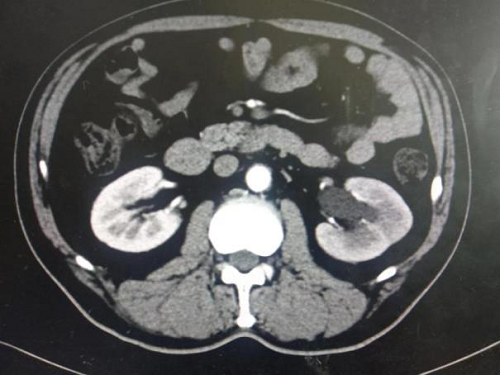

辅助检查:完善泌尿系CTU示腹主动脉下段、双侧髂总动脉周围见软组织影环绕,可见延迟强化,于左侧髂总动脉水平病变与左输尿管分界不清,相应水平左输尿管狭窄,以上输尿管,肾盂、肾盏扩张积水,腹腔、腹膜后未见明显肿大淋巴结。(如下图1-4)

(图1-4泌尿系CTU示考虑腹膜后纤维化累及左输尿管致尿路梗阻)